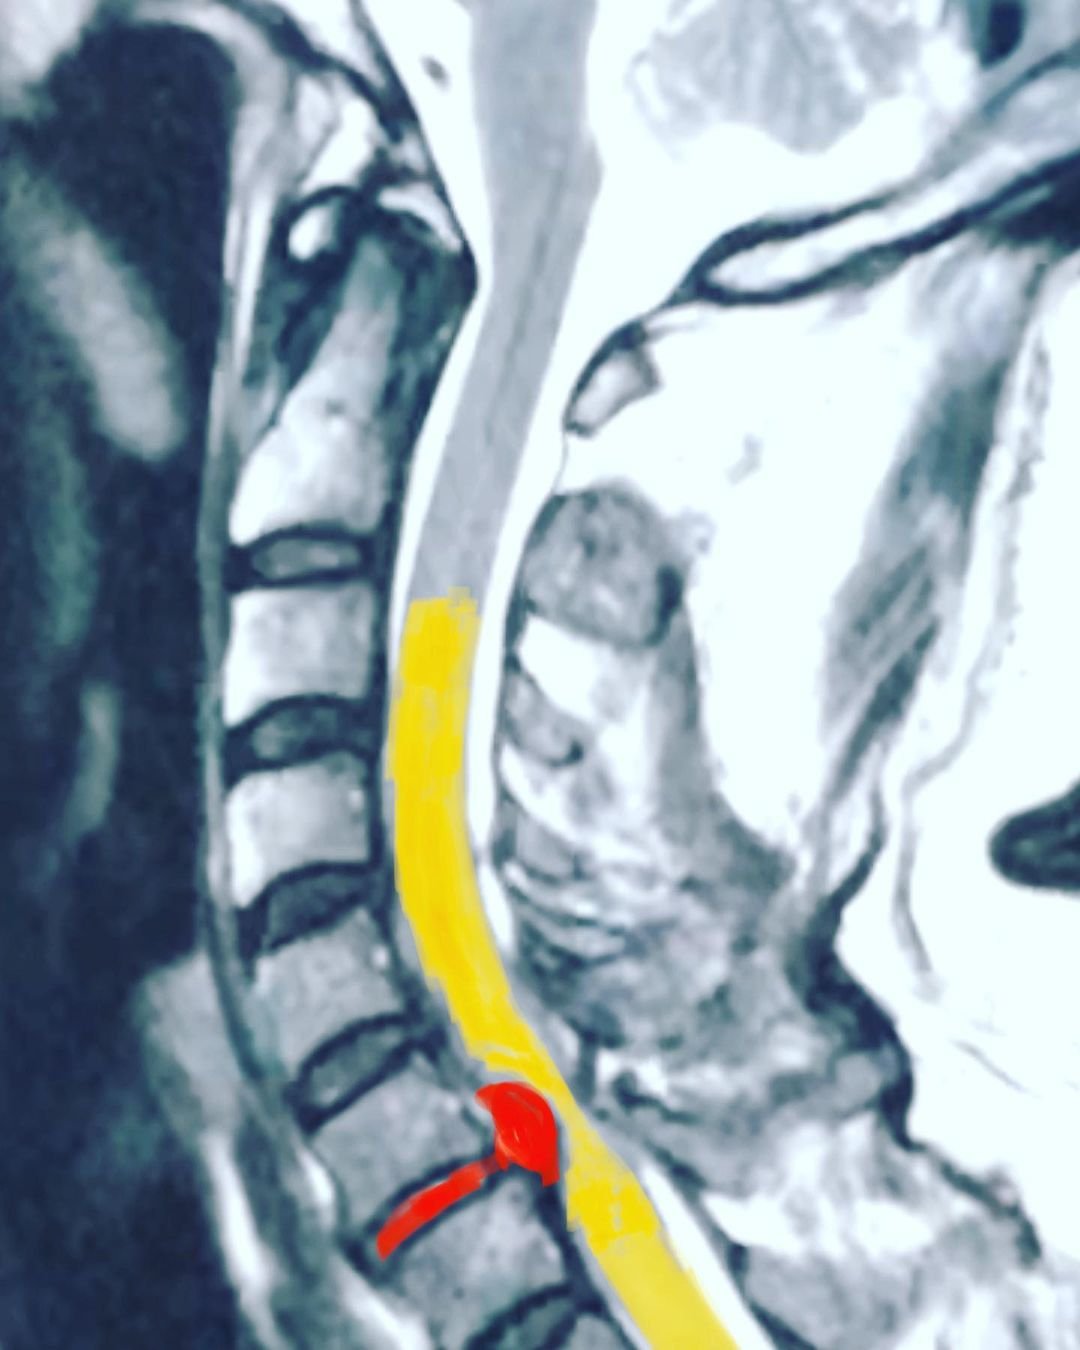

Hernia de disco

Ciática